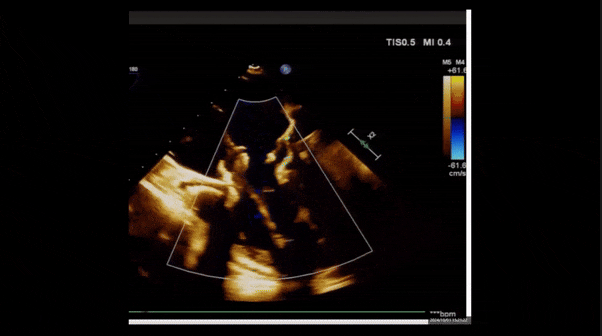

2、彩色多普勒顯示:收縮期三尖瓣口返流束起源于后隔交界、前后葉之間及前隔交界,返流束縮流頸最大寬度27mm,三尖瓣返流口EOA=2.02cm2,返流容積124ml,收縮期三尖瓣返流峰值速度2.64m/s,返流峰值壓差28mmHg,PAPs 43mmHg,舒張期三尖瓣口平均跨瓣壓差1mmHg,肝左靜脈可見明顯逆向血流波。

術后即刻返流

術后即刻經食道超聲可見,三尖瓣假體瓣膜位置合適,牛心包瓣葉運動狀態良好,開閉正常,瓣周及瓣葉對合緣處未見明顯返流,心電圖及心包狀態較術前無明顯變化。

術前術后返流情況對比